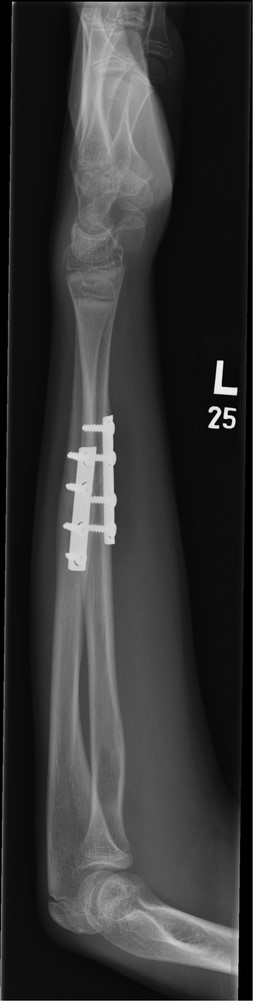

A 12-year-old male patient sustained a closed midshaft both-bone forearm fracture of their non-dominant arm from a fall on a trampoline (Figs 1 and 2). Anatomical reduction was achieved with a manipulation under anaesthesia (MUA), but it was noticed that there was a mechanical block to extension of the ring finger. The radius and ulna were therefore approached through separate incisions and it was discovered that the FDP was entrapped at the ulna fracture at the level of the musculotendinous junction. Following release the fingers regained a full range of motion and the patient went on to heal without further complication (Figs 3 and 4).

Three months post-operative lateral radiograph showing radiological union.